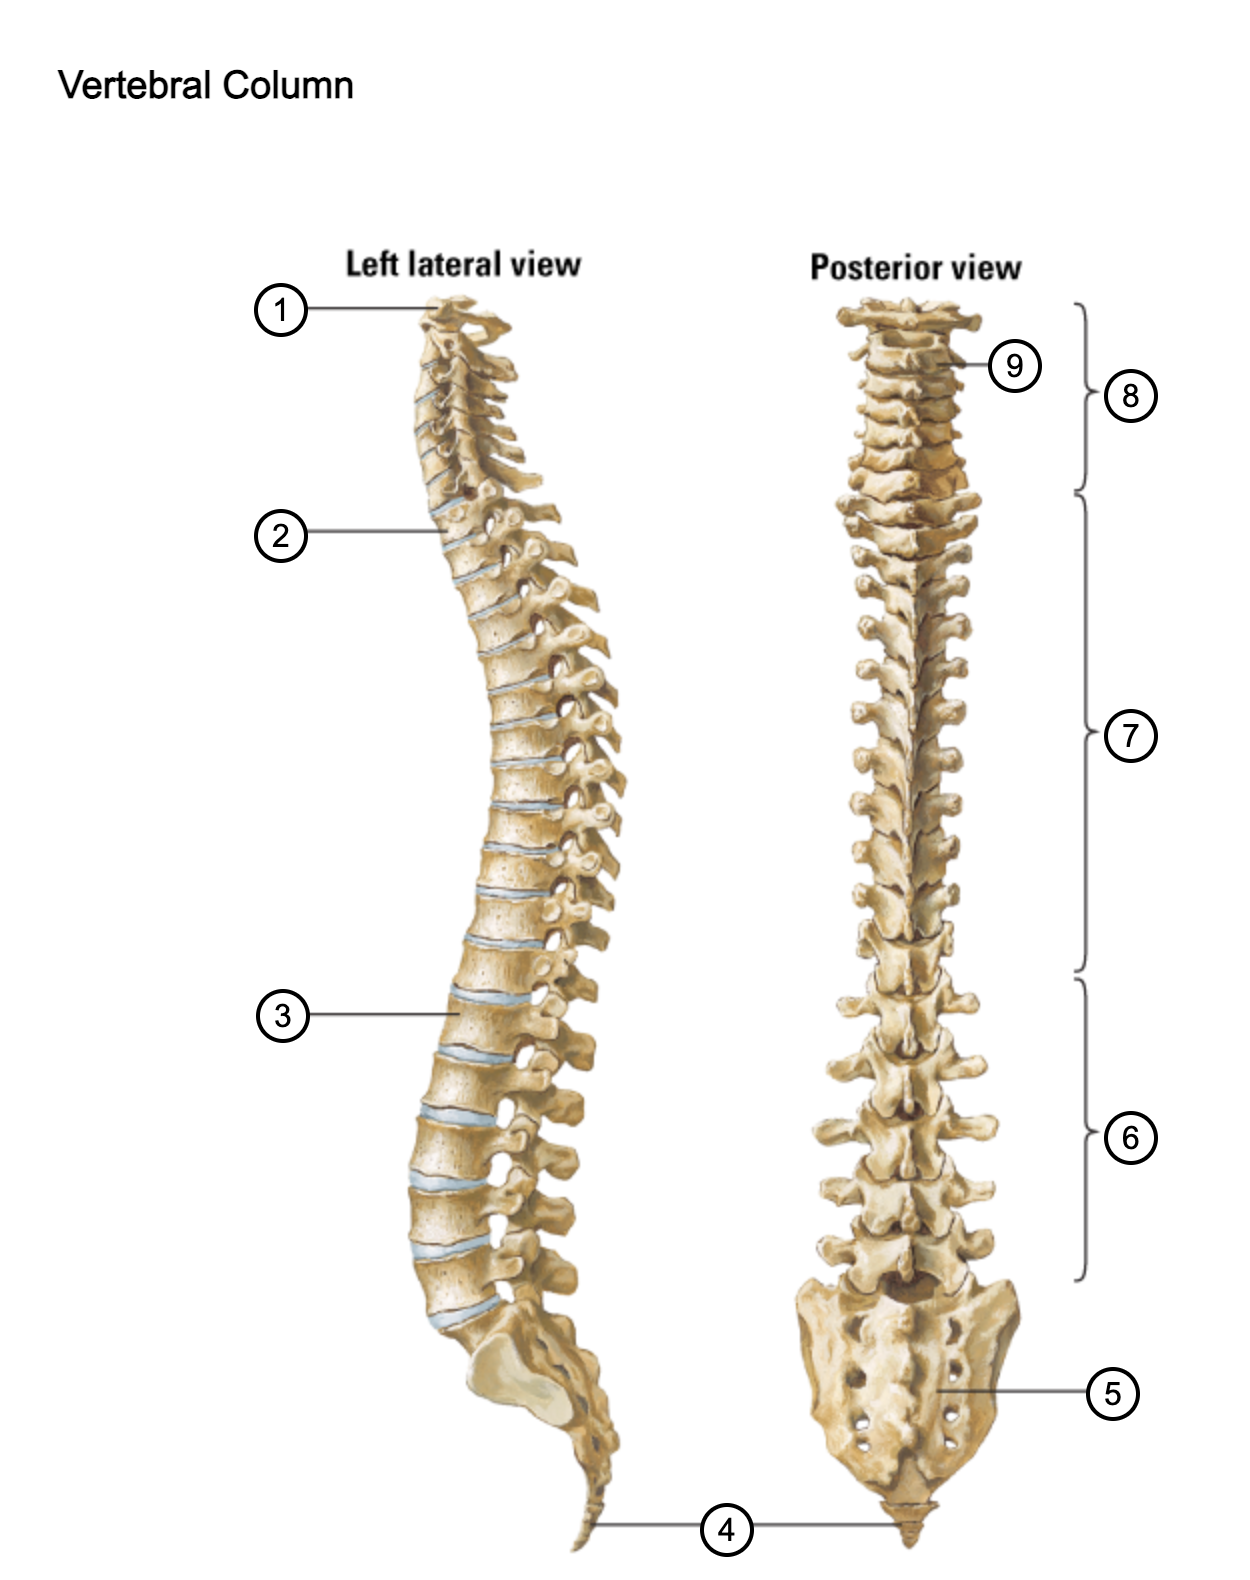

1

atlas (C1)

2

T1

3

L1

4

coccyx

5

sacrum (S1-5)

6

lumbar vertebrae

7

thoracic vertebrae

8

cervical vertebrae

9

axis (C2)